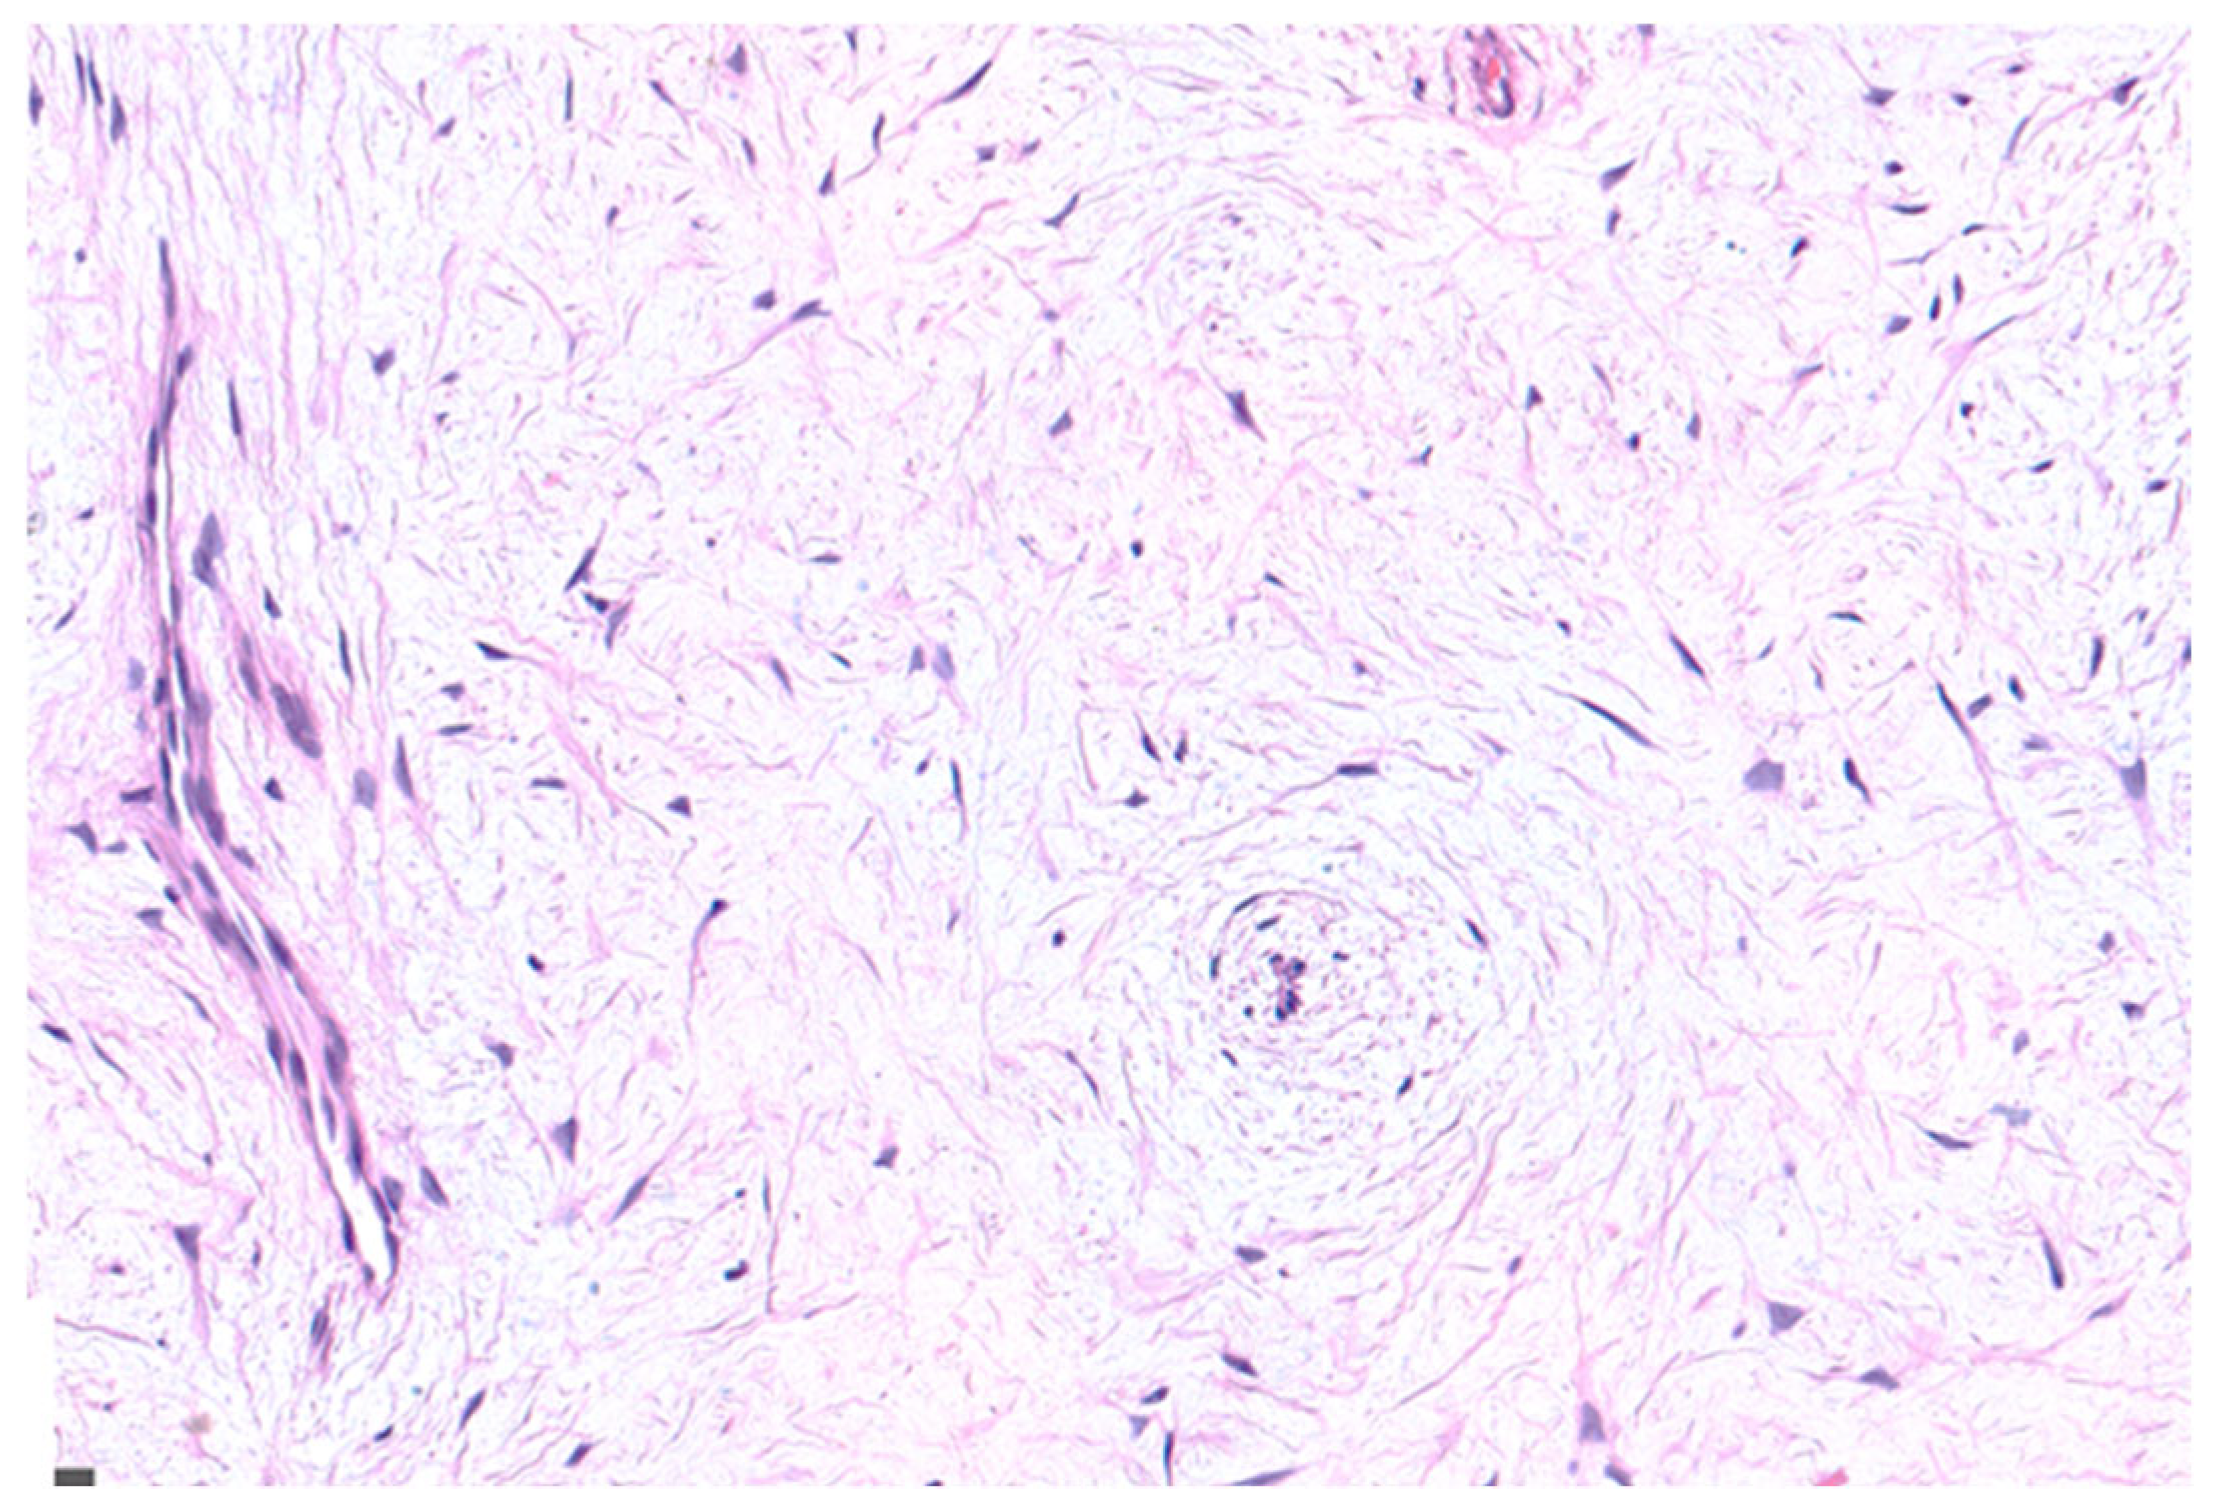

2.1. Case Presentation